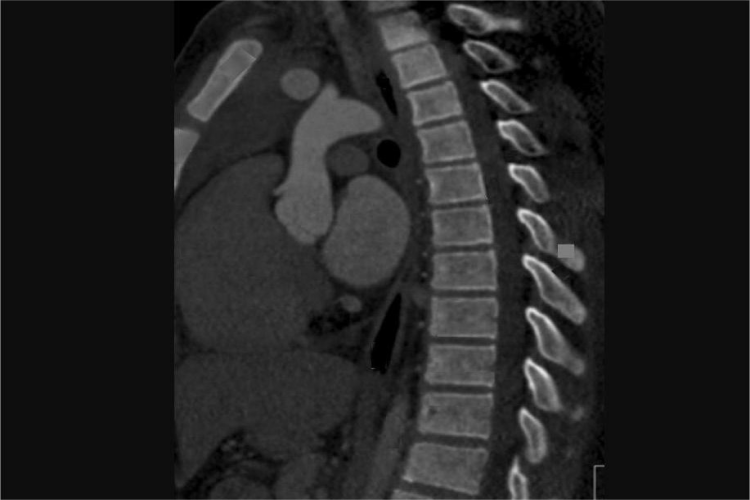

一般情况下,胸椎CT片成像可显现12节胸椎及12个椎间盘,胸椎的椎体比颈椎高大,椎体上下面平坦,后侧略高。胸椎后关节面平坦,与脊柱中线平行,上关节面向后朝下,下关节面向前朝上。可辅助用于机体对胸部疾病的诊断与治疗。